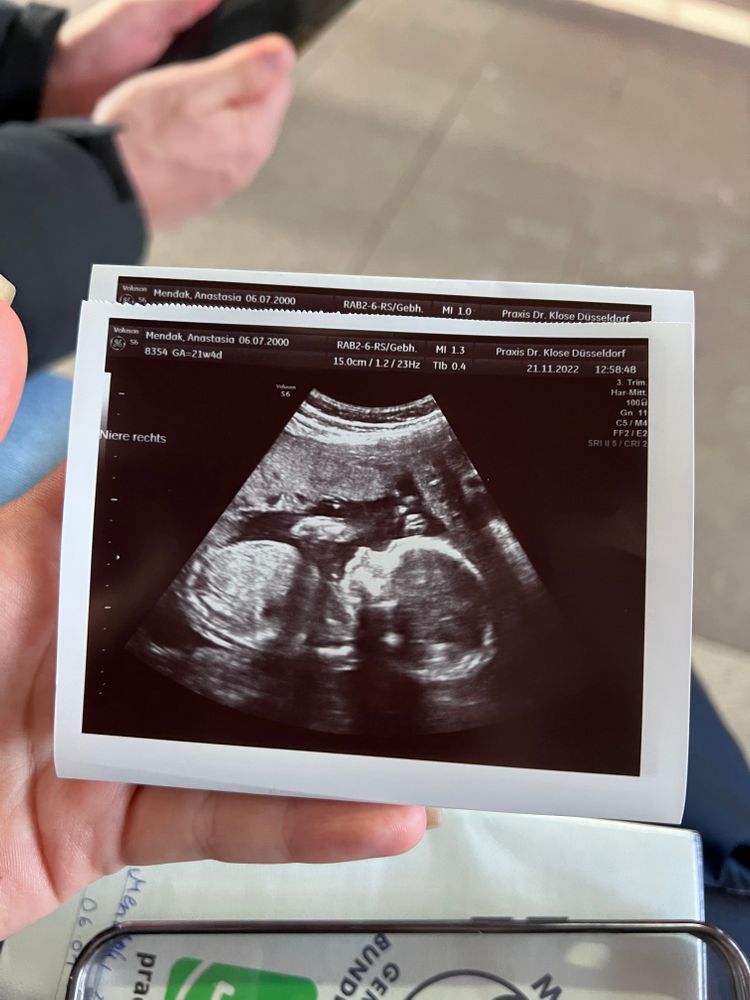

Почти закончился 6 месяц беременности а мне так и не могут сказать кто у меня родится. Через пару дней на узи, но не факт что скажут, старый аппарат и врач скорее не опытный. Я сейчас нахожусь на 25 неделе. Последнее фото было месяц назад на 21 неделе. На первом узи сказали что 80% мальчик(1фото). На втором узи сказали что ничего непонятно. На третьем сказали что возможно девочка, но ничего не видно. Помогите, пожалуйста, определить пол🐰

По таким фото не видно (ракурс и мелкие). Делают для точности узи попой снизу, чтобы видно было, что между ножек...странно,писюн не заметить, может, и правда тогда, пол женский. Но это всё домыслы. Сделайте в другом месте узи

У вас фото какие-то не удачные , в том смысле , что на них не видно пол, даже предположить не возможно. Я на последних двух вообще не пойму что изображено.